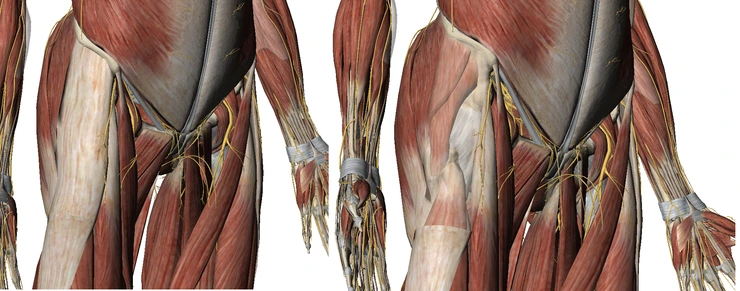

고관절은 둔부의 많은 근육들이 주변에서 지나가게 됩니다. 특히 고관절의 외측에는 대퇴근막장근과 장경인대, 그리고 둔근의 일부 섬유들이 지나가게 되는데, 이 구조들이 대퇴골의 결절을 지날 때 소리를 발생하게 합니다.

좌측의 경우 대퇴근막장근이 표시되어 있는 그림이고, 오른쪽의 경우 대퇴근막장근을 약간 불투명하게 처리해서 그 안에 대퇴골의 결절이 보이도록 처리한 것입니다. 이 사진은 좀 더 큰 사진으로 올렸기에 클릭하면 더 크게 보실 수 있습니다.

대퇴근막장근과 장경인대가 가장 표층에서 측면을 지나고, 그 아래에는 둔근의 전면부 섬유가 건(힘줄)이 되어 대퇴골두 주변에 와서 붙게 됩니다. 이 때 대퇴근막장근과 장경인대, 혹은 대소중둔근의 섬유가 단축이 되어 그 길이가 짧아졌다면 평소에는 넉넉한 길이로 대결절 위를 지나던 것이 더 단단한 상태로 대퇴골을 압박하면서 대퇴골의 뼈에 의한 작은 융기부분들을 스치면서 지나가게 될 것입니다. 이런 경우 소리와 함께 압박하는 조직의 손상이 발생할 것입니다.